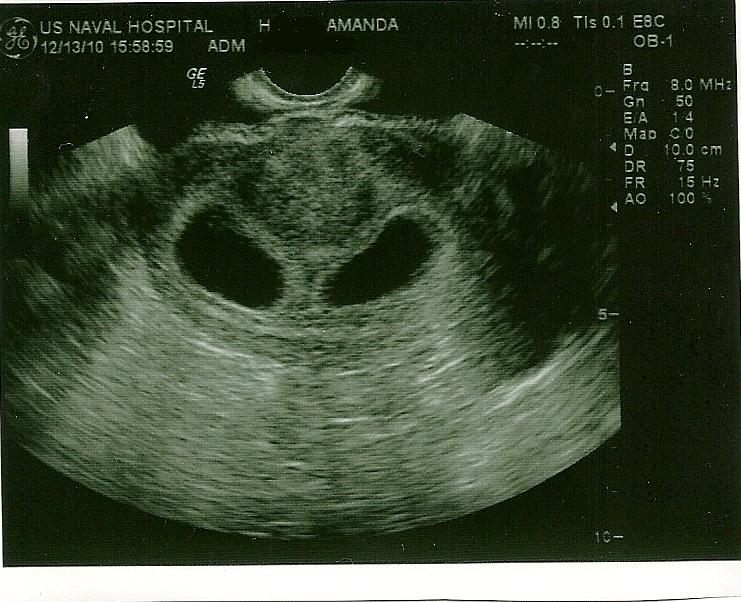

Babies babies! We got to see them again today... with pictures this time!

This one shows both of the sacs together-you can't see the babies because of the angle, but you can see that there are indeed two in there and the ultrasound machine wasn't playing tricks on us!

We thought it was soooo hilarious when the doc checked for triplets (you can sense the sarcasm right?) ...it was a really good visit, a lot of our basic questions were answered. I was put on extra iron and extra folic acid, and put on Zofran for the nausea instead of the Benadryl. I'm still nervous, since having multiples puts us at higher risk for miscarriage. I'll be super glad when the first trimester is over. Only 40 days to go!

We thought it was soooo hilarious when the doc checked for triplets (you can sense the sarcasm right?) ...it was a really good visit, a lot of our basic questions were answered. I was put on extra iron and extra folic acid, and put on Zofran for the nausea instead of the Benadryl. I'm still nervous, since having multiples puts us at higher risk for miscarriage. I'll be super glad when the first trimester is over. Only 40 days to go!Next appointment is about 2 1/2 weeks from now-which was supposed to be my "initial visit". I'll get another ultrasound then! I'll be sent for Level 2 ultrasounds in Charleston or Savannah every so often to check growth and progress more thoroughly, not sure when they start or how often I'll go. I'm excited to be able to see these little babes more often!